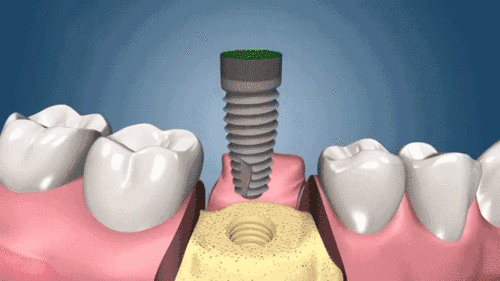

1、種植牙的醫(yī)療設(shè)備要求高,種來(lái)自植技術(shù)需要配備較高的設(shè)備環(huán)境,例如大型X線診斷設(shè)備、臨床手術(shù)設(shè)備、技工設(shè)備、手術(shù)支持設(shè)備以及在義齒制作時(shí)需要的一些獨(dú)特的較貴重的修復(fù)材料。這是影響上海種植牙價(jià)格的另一個(gè)因素。2、種植牙材料成本高決定了上海種植牙價(jià)格,種植體的加工工藝復(fù)雜且要求極其。目前,世界上較著名的種植系統(tǒng),例如瑞典NOBEL種植系統(tǒng),種植體于滿足不同的修復(fù)設(shè)計(jì)需要,所以上海種植牙價(jià)格高。

3、種植牙對(duì)醫(yī)護(hù)人員的要求高,進(jìn)行種植牙修復(fù)的人員必須是經(jīng)過(guò)專業(yè)的培訓(xùn),包括種植外科醫(yī)生,種植修復(fù)醫(yī)生,種植技師和相關(guān)的種植助理共同來(lái)完成,這樣所花費(fèi)的人員成本較高也就影響了上海種植牙價(jià)格。